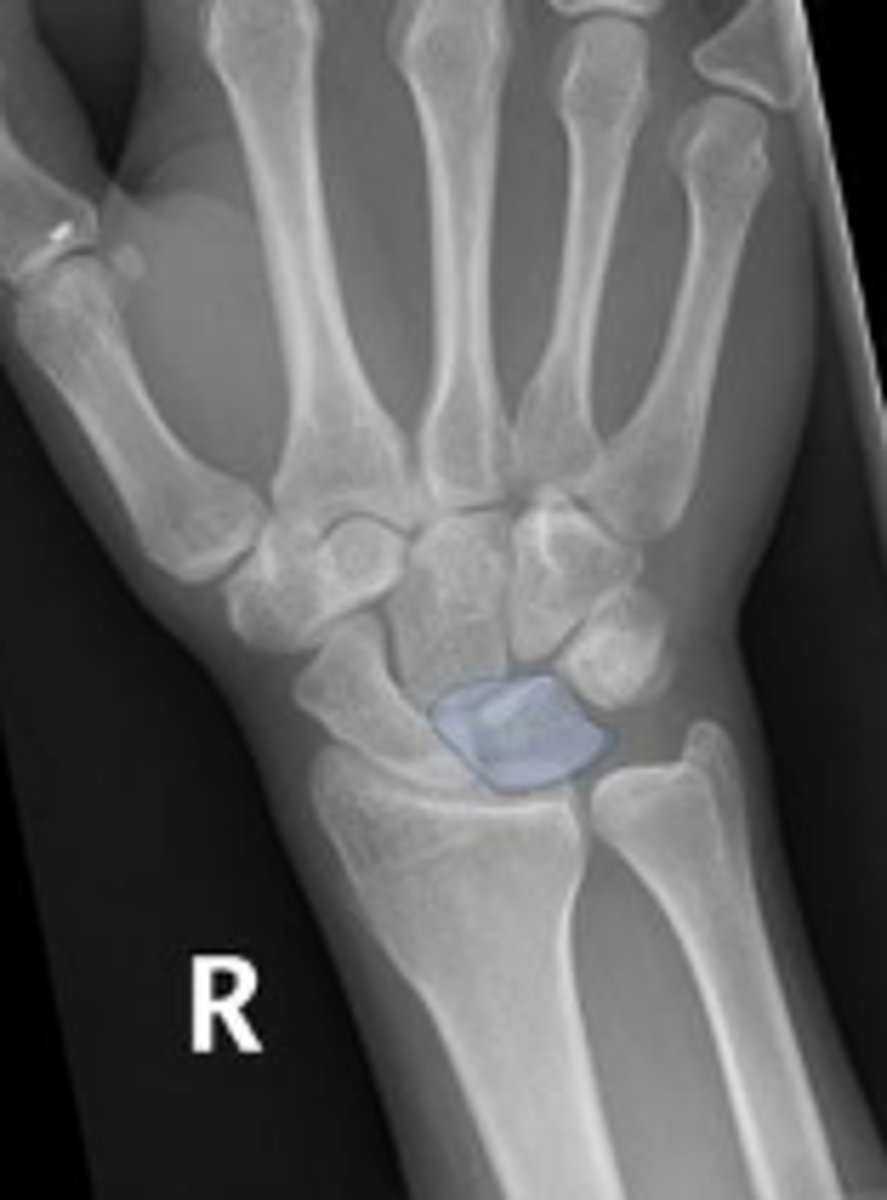

Right scaphoid

What is outlined?

What is the arrow pointing to?